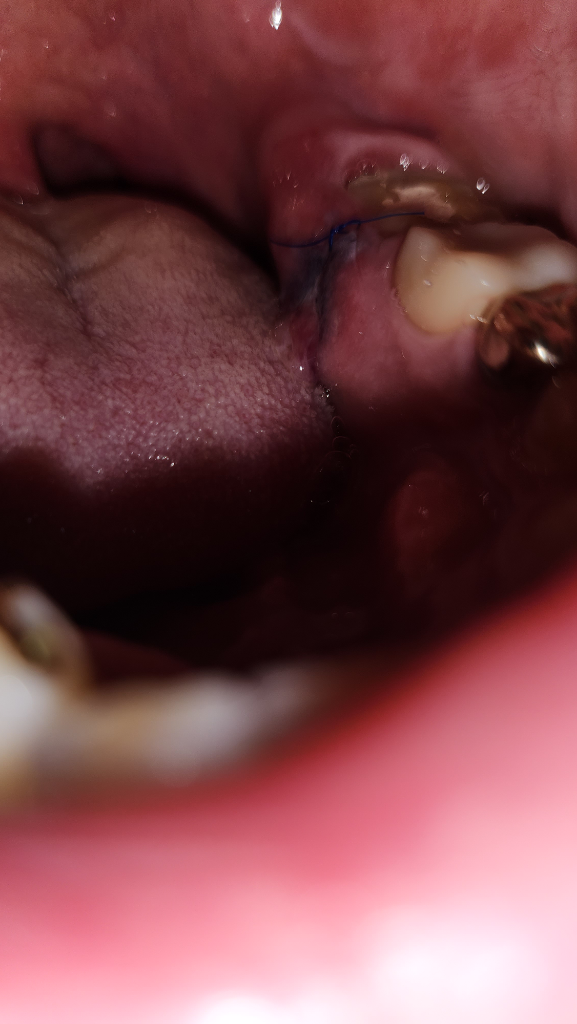

1. 안쪽 잇몸은 부풀어 있던 잇몸이라 잇몸이 늘어졌다고 표현해야할까요 잇몸 표면이 축 쳐져 있습니다

이건 괜찮은가요?

현재 사진상 문제가 되지는 않습니다.